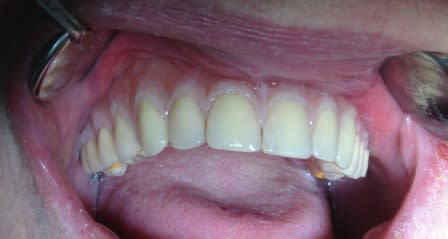

quand il y a peu d'os!!

lundi :pose des implants empreinte et occlusion

mercredi :essayage de l'armature et montage esthétique

vendredi : pose de l'ensemble

le bridge agit comme un fixateur externe , 3 mois d'alimentation molle